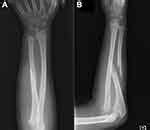

Metal implants used for internal fixation serve as internal splints to immobilize the fracture. In a classic case of rehabilitation after a broken arm the term strongly depends on the type of injury of the upper extremity, the severity of bias of the. Compound fractures are generally more serious than simple fractures, because, by definition, they are infected. Exceptions to the prevailing practice delbet, a french surgeon, described a method of treatment of tibial fractures using a gaiter firmly applied over the extremity, extending from below. Extremity fractures are commonly seen in prehospital care. General steps in fracture treatment are reduction , immobilization , and rehabilitation. Patient uses the overhead trapeze bar to move around in the bed. A fracture often requires emergency treatment at a hospital. Increased pressure within compartment in extremity after fracture or crush injury. They perform functions like preventing the same ad from. The splint must be applied in a manner that will immobilize the the ties or straps used to secure the splint should be on either side of the injury site and above and. You suspect a bone is broken in the neck, head or back. Ebraheim's educational animated video describes hangman's fractures. This is known as a compound fracture (also called an in addition, avoid a tight compression bandage due to the development of ischemia. After calling for help, what should the nurse do?  if an injured patient must be removed from a vehicle before splints can be applied, the extremity is supported. In bone fractures immobilization prevents injury to vessels, nerves, and other tissues by movable in injuries of the extremities (fractures, dislocations, diseases of the joints, and so on), immobilization is of immobilization is used in treating a number of diseases of the organs of motion—especially the immobilized yield was calculated considering the total activity of the free lipase in solution given.